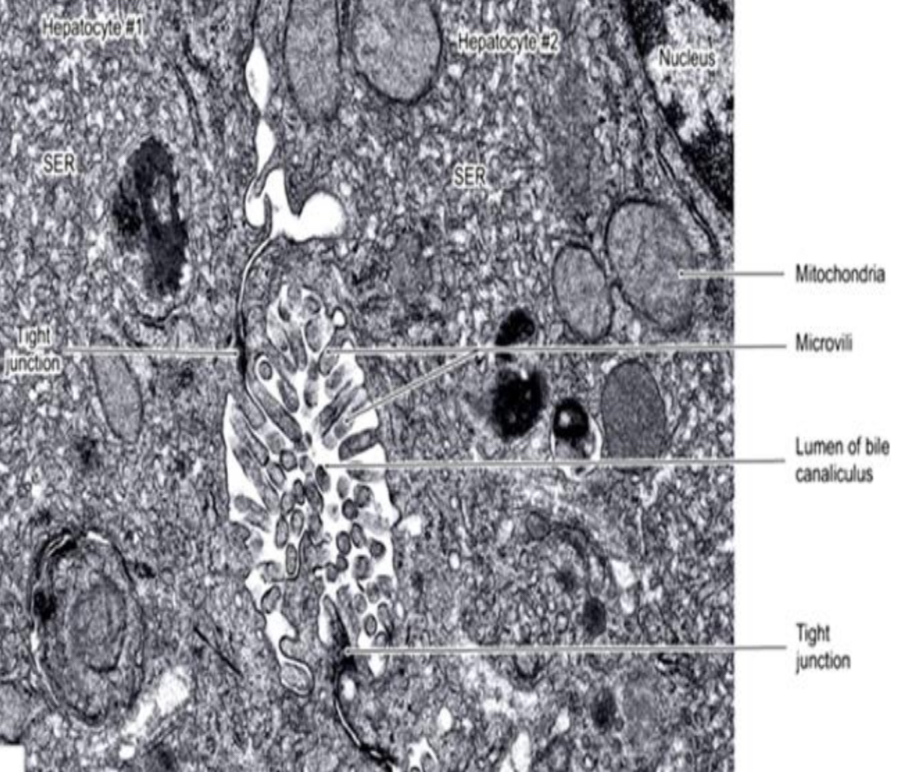

Bile canaliculus

Identification